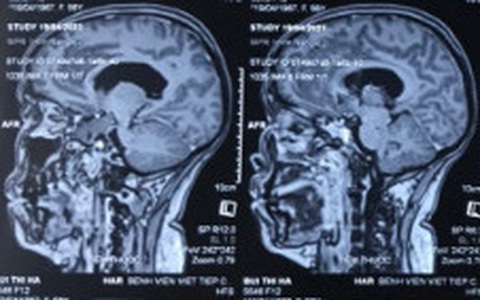

Đau đầu là triệu chứng thường gặp trong các bệnh lý thần kinh và mạch máu não. Đặc biệt, cơn đau đầu dữ dội - “đau đầu sét đánh” cảnh báo tình trạng nguy hiểm khi túi phình mạch não dọa vỡ hoặc vỡ.

Một phụ nữ 56 tuổi (ở Hải Phòng) kể một năm nay thường xuyên đau đầu, bà nghĩ có thể do thiếu máu lên não, nhưng uống thuốc bổ cũng không đỡ.